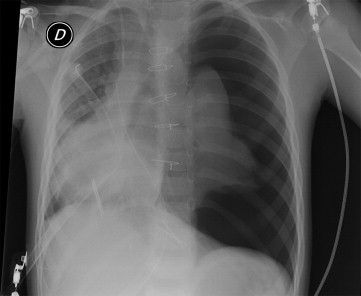

Luxatio cordis refers to dislocation of the heart. This condition is a rare complication of blunt trauma to thorax. The management involves stabilizing hemodynamic status followed by surgical repositioning of the heart and repair of pericardial tears. Reference: https://pubmed.ncbi.nlm.nih.gov/12122540/ Image via: https://www.annalsthoracicsurgery.org/article/S0003-4975(12)02801-9/fulltext